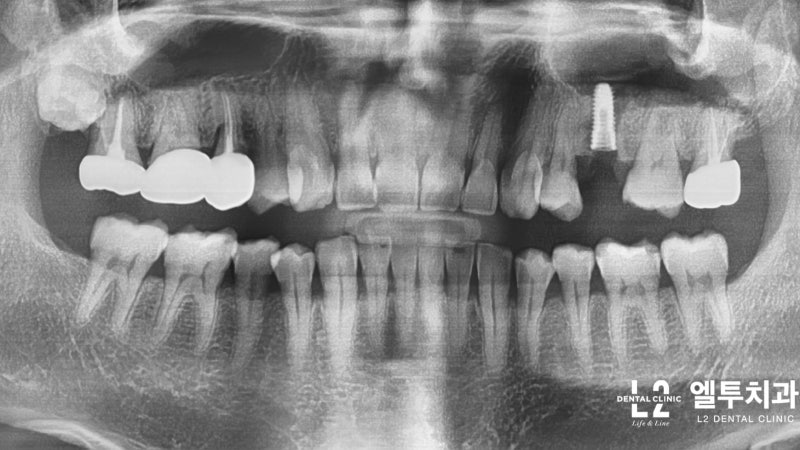

오늘은 작은 어금니 부위의 씹는 통증 때문에 저희 병원을 찾아오신 환자분의 사례인데요, 이전에 치근 치료를 받았던 작은 어금니 부위는 치아 머리부터 뿌리까지 깊은 균열(균열)이 있었습니다. 근관 치료 및 크라운 치료 . 무수히 많은 치아를 뽑고 임플란트를 식립한 사례입니다.

큰어금니와 작은어금니의 갈라진 치아 모습에는 차이가 있는데, 큰어금니의 갈라진 치아는 대부분 “기능적 팁” 쪽, 즉 치아에서 더 큰 스트레스를 받는 부분에서 발생합니다. (아래 포스팅 참조) https://blog.naver.com/sunnyflow/222654941394 Q-ray 촬영으로 어금니 크랙(균열)을 미리 확인하고 대비할 수 있습니다. 닥터&치주과의사 최순호 입니다 오늘은 어금니 중문으로 가는데… blog.naver.com 물론 기능교두의 기능교두는 작은 어금니에도 크랙이 생기는 경우가 많은데, 치아가 부러지는 원인. 음식을 씹을 때 위아래로 씹지 말고 나란히 씹는다. 이것을 치과 용어로 “Lateral Guidance”라고 하는데 위 사진에서 색종이(교합용지)를 찍으면 치아에 가해지는 힘이 화살표 방향으로 퍼지는 것을 볼 수 있습니다. 다시 케이스로 돌아가서 왼쪽 위 어금니가 이전에 근관치료와 크라운 치료를 받았고 씹을 때 불편하다고 하셨습니다. X-레이를 보면 치근/크라운 치료를 받은 어금니 주변에 어두운 그림자가 보일 것입니다. 뼈가 녹으면서 “J자 모양”이 되고 X-레이에서 보이는 이러한 방사선학적 변화는 종종 치아의 깊은 층에 균열이 있음을 나타냅니다(크라운 뿌리 균열, 뿌리 균열 = 치근. 갈라진 치아). 측방 구강 내부에서 송곳니가 곧게 연마되는 것과 같이 측면 안내 중에 치아가 강한 측면 힘을 받는 것으로 추론할 수 있습니다. 이 힘이 계속되면서 작은 어금니 부위에도 깊은 균열이 발생했다. 이 정도까지 치아 사이의 간격이 벌어지면 치과에서 치료할 방법이 없기 때문에 발치 후 임플란트 치료를 권해드립니다. 발치 모습. 화살표가 가리키는 부분을 자세히 보면 치아의 머리 부분에서 시작하여 치근 깊숙이 뻗어나가는 크랙(균열)을 볼 수 있습니다. 입 안의 세균이 미세하게 새는 것은 균열선을 따라서만 진행될 수 있어 잇몸뼈가 재흡수되어 씹을 때 통증이 발생합니다. 임플란트 수술은 발치 당일에 시행하고 일정 기간 치유 후 작은 어금니 부위에 임플란트 크라운을 식립합니다. 이러한 현상을 가진 환자들은 이상한 점을 발견할 수 있는데, 반대측 치아에서도 비슷한 상황을 관찰하는 경우가 매우 흔하다. 반대쪽 소구치를 보면 잇몸뼈가 주변 치아와는 매우 다른 방식으로 흡수되는 것을 볼 수 있습니다. 이 치아 역시 치근 치료와 크라운 치료를 한 치아이기 때문에 치아의 치근쪽에 크랙이 나타난 것으로 의심됩니다. 문제 치아 옆의 작은 어금니도 균열이 의심되는 Q-선 형광 검사에서 관찰되었습니다. 금이 간 치아가 강하게 의심되었지만 어쨌든 심각한 치은 골 흡수가 관찰되었으므로 “진단”+ “치료”의 목적으로 치은 박리를 시행했습니다. (환자분들이 아프지 않을때까지 보관하라고 하셔서 알고 있습니다.) 이렇게 입에 금이 간 치아가 많은 분들은 예방적 크라운 치료를 권해드리고 있습니다. 크라운 치료는 앞니의 단점이 있지만 “치아 보호”가 최우선입니다. 위에서 언급한 2개의 치아 외에도 양쪽 소구치에 크랙이 관찰되어 더 진행하면 바로 발치할 수 있어 환자에게 크라운 치료를 알리고 진행하였다. 너무 늦기 전에… 깨진 치아를 무시하면 종종 손을 사용하지 않고 발치 및 임플란트 치료가 발생할 수 있습니다. https://blog.naver.com/sunnyflow/222413456775 치아가 깨지거나 부러져 부주의로 발치를 하게 된 사례 안녕하세요. L2치과의원장 최순하오 원장입니다. 최근 치과에 다녀온 환자에서… blog.naver.com 바로 씹어도 통증이 없어도… 상당한 크랙이 관찰된다면 예방적 크라운 치료를 고려해보시는 것을 강력히 추천드립니다:) 오늘의 기사가 도착합니다. 끝. 스마트폰에서 위 부분을 터치하시면 다이얼로 전환됩니다.서울시 강남구 봉은사로 469, S-TOWER L2, 4층 치과